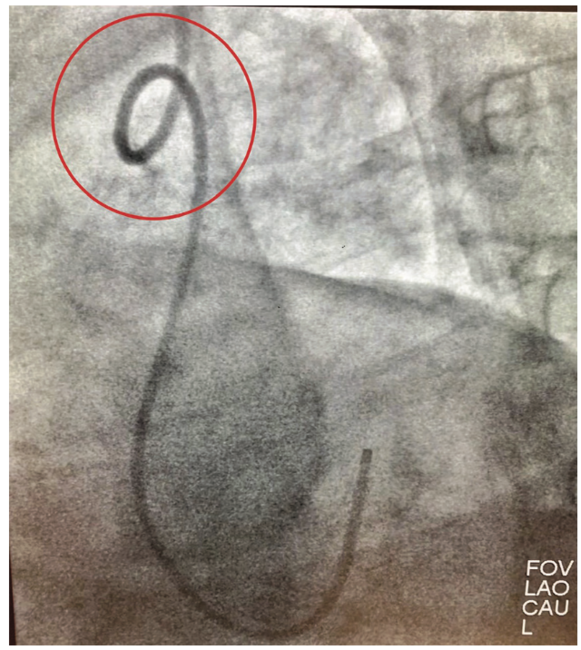

Entrapment of a Kinked Catheter in the Radial Artery During Transradial Coronary Angiography Catheter Kinked this occurs when a catheter cannot drain and is most commonly caused by the catheter or tubing being kinked or occluded, or by constipation or the weight of a full catheter bag pulling the balloon into the bladder neck. Diagnostic coronary artery catheter knotting and kinking are uncommon but potentially catastrophic complications. make sure the tubing is not. Catheter Kinked.

From www.radcliffecardiology.com

Figure 6 The Way to Catheter Kink in the Right Radial Artery in Case 3 Radcliffe Catheter Kinked check for kinks in the catheter or drainage bag tubing. In some cases, your catheter may need to be changed. If the drainage bag tubing or catheter is twisted, kinked, or being pressed against your body with too much pressure, such as under clothing or a leg strap, then the urine will not flow freely. this occurs when. Catheter Kinked.

(PDF) Removal of a catheter kinked in the radial artery by anchoring the distal part of the Catheter Kinked Catheter blockage is an emergency and needs to be resolved as quickly as possible. Diagnostic coronary artery catheter knotting and kinking are uncommon but potentially catastrophic complications. below you’ll find information on some of the associated risks and problems you may encounter with a catheter. if there are no kinks in your catheter or tubing, it is possible. Catheter Kinked.